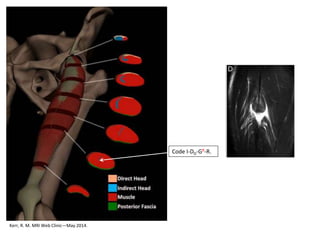

Kerr, R. M. MRI Web Clinic—May 2014.

• For the proximal MTJ

we describes if the

injury locates

• conjoined tendon P

• at the direct P1

• indirect P2

Code I-PP-G-R.

Code I-P1-G-R.

Code I-M2-G-R.

Code I-M2-GR-R.